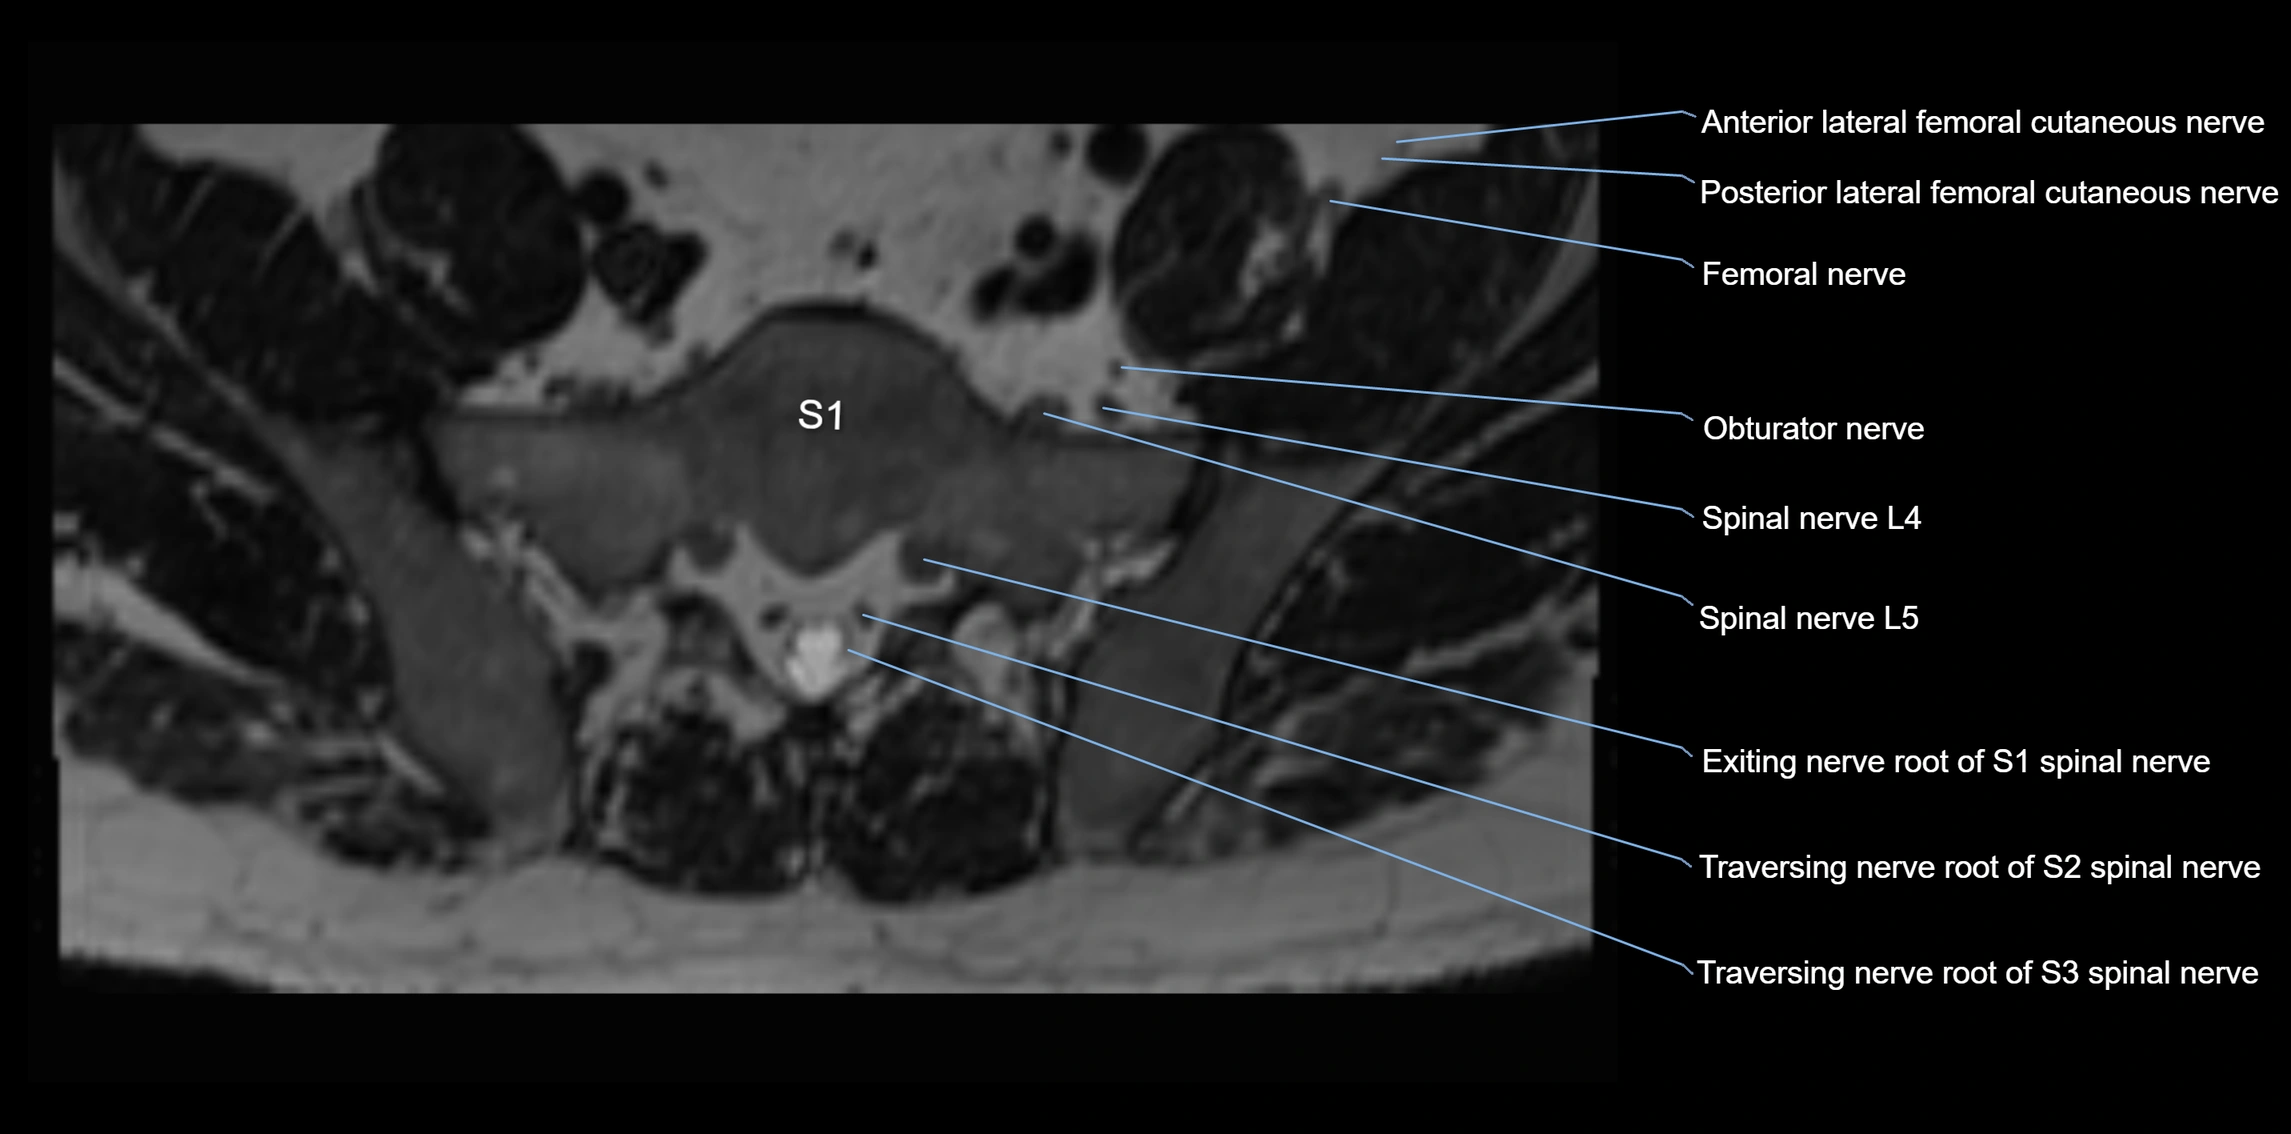

MRI Appearance

T1-weighted images:

• Nerve appears as a very thin low-to-intermediate signal intensity structure

• Surrounded by bright fat, aiding visualization

T2-weighted images:

• Nerve shows intermediate to mildly hyperintense signal compared to muscle

• Pathological involvement appears brighter

STIR (Short Tau Inversion Recovery):

• Normal nerve appears dark

• Inflamed or entrapped nerve appears bright hyperintense

T1 Fat-Sat Post-Contrast:

• Normal nerve enhances minimally

• Pathologic nerve (neuritis, entrapment, tumor infiltration) shows focal or diffuse enhancement

3D T2 SPACE / CISS:

• Nerve appears intermediate to mildly hyperintense compared to muscle

• Surrounded by bright fat or CSF, improving visualization

• Best sequence for mapping small pelvic nerves such as the anococcygeal

MRI image

image